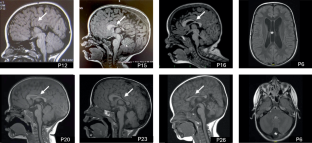

The CCR4-NOT complex, crucial in gene expression regulation, includes CNOT3, a subunit linked to neurodevelopmental disorders when mutated. This study investigates 51 patients from 42 families with heterozygous CNOT3 variants, aiming to expand the understanding of CNOT3-related neurodevelopmental disorders and explore genotype-phenotype correlations. Patients originated from various countries, reflecting the disorder’s global significance. All patients exhibited developmental delays, particularly in the language area. Intellectual disability was found in 87% of patients and was typically mild to moderate. Behavioral issues, including autism spectrum disorders and attention deficits, were common, affecting over half of the patients. Dysmorphic features were highlighted and may help establishing the diagnosis. Epilepsy was uncommon (10%). Twenty-eight novel variants were identified, including missense, nonsense, frameshift, intronic variations and a deletion of 12 exons. Missense variants clustered at the N- and C-terminal regions of the protein, indicating critical functional roles. No clear genotype-phenotype correlation was observed, suggesting that all identified variants resulted in a loss-of-function effect. Finally, this work delineates the clinical and molecular spectrum of CNOT3-related disorders thanks to an in-depth characterization of a large cohort. Further research will be necessary to understand the functional consequences of the variants and enhance patient long-term outcomes.